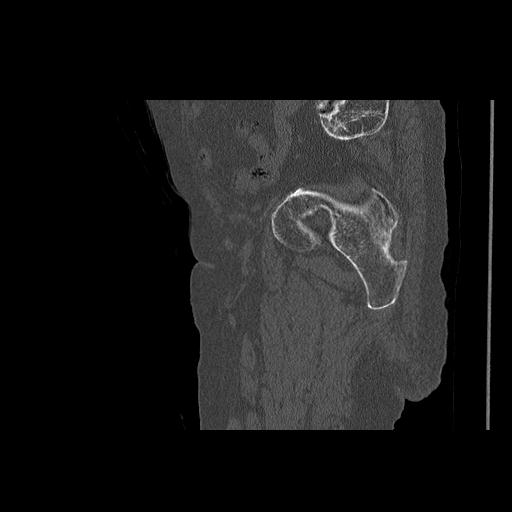

46666 1/28 両股正面+軸と 1/26 右手関節 2R 76歳女性 右転子部骨折